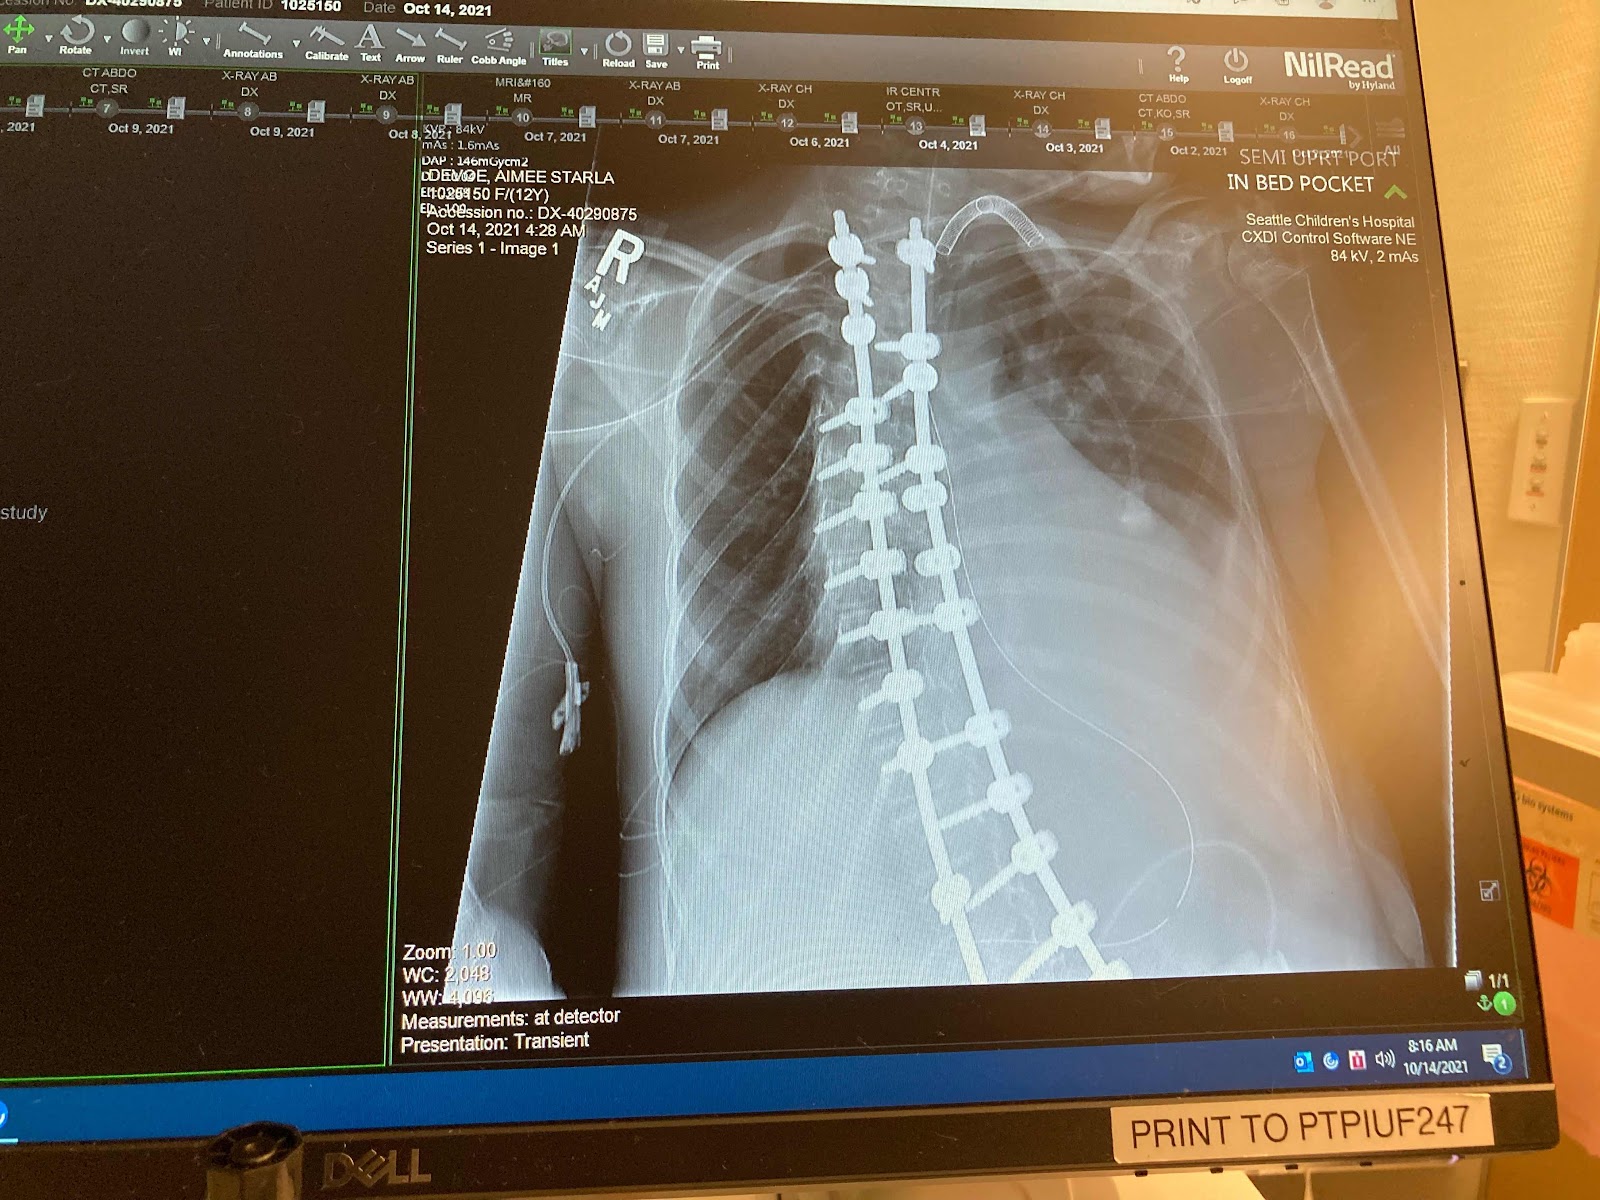

After a fairly quiet day yesterday, today came in more dramatically. The team had an x-ray done in the wee hours of the morning (about 3:45) and noted that there increasing indication of pneumonia in her left lung compared to yesterday. They had been noting all day yesterday how diminished her lower left lung sounded. Her sepsis markers in her blood have increased again significantly. Her fevers have continued. They are starting her on a broad antibiotic that would cover that and the growth from her abdominal incision infection while they wait for the tracheal secretion labs to come back. Today her secretions have increased and appear yellow. So far she is stable as far as respiratory support is concerned.